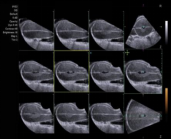

ACUSON Juniper 超声诊断系统的探头使用创新超低损耗透镜材料和微电子技术,实现高效性能和增加信号带宽,从而可获得优异的图像质量。西门子弹性成像 VTQ 声触诊组织定量技术,利用声脉冲辐射力(ARFI)原理,临床可用于间接无创检查肝组织硬度,进而区分肝纤维化过渡阶段;且是基于可视超声二维图像条件下进行定量分析,故其临床重复性好,得出高精度测量数据,测值单位 m/s 或 KPa 任意可选。西门子 VTQ 技术在慢性乙型和丙型肝炎纤维化的诊断和监测具有一定的意义。